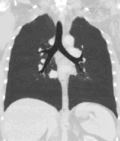

A CT scan can be used for detecting both acute and chronic changes in the lung parenchyma, the tissue of the lungs.[66] It is particularly relevant here because normal two-dimensional X-rays do not show such defects. A variety of techniques are used, depending on the suspected abnormality. For evaluation of chronic interstitial processes such as emphysema, and fibrosis,[67] thin sections with high spatial frequency reconstructions are used; often scans are performed both on inspiration and expiration. This special technique is called high resolution CT that produces a sampling of the lung, and not continuous images.[68]

Computed tomography angiography (CTA) is a type of contrast CT to visualize the arteries and veins throughout the body.[111] This ranges from arteries serving the brain to those bringing blood to the lungs, kidneys, arms and legs. An example of this type of exam is CT pulmonary angiogram (CTPA) used to diagnose pulmonary embolism (PE). It employs computed tomography and an iodine-based contrast agent to obtain an image of the pulmonary arteries.[112][113]